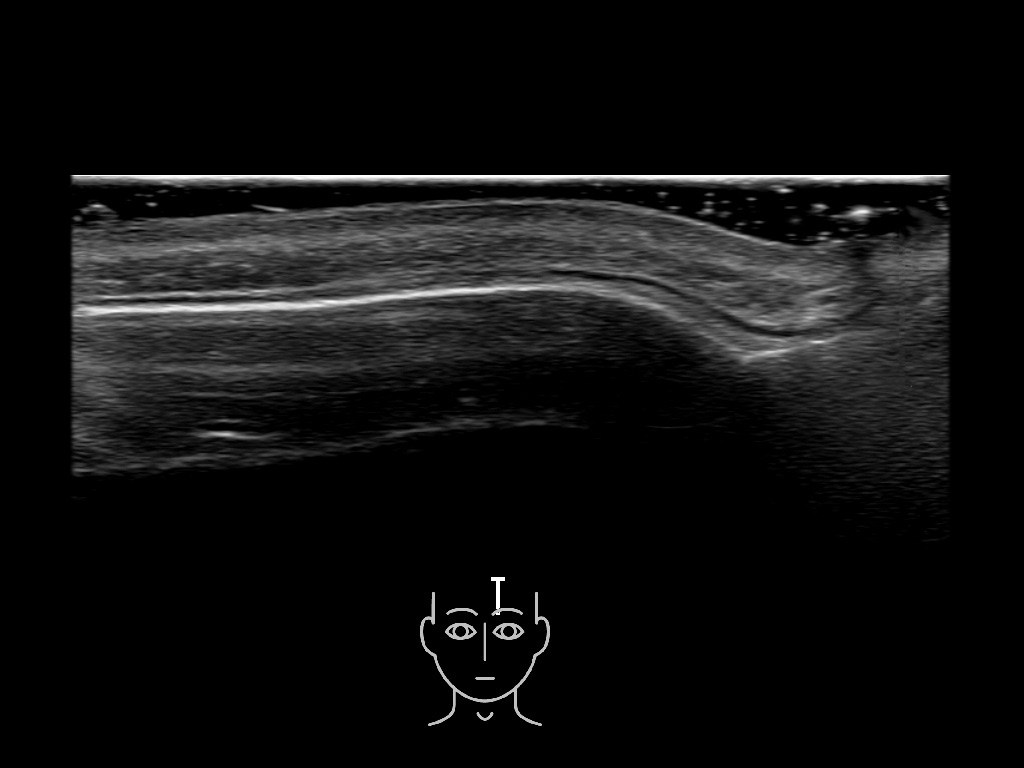

In this section you will learn more about the different layers of the face with the use of ultrasound. When you click on the secondary ultrasound image, you will see the different structures as an overlay. This will help to train yourself to recognize the different layers of the face.

Study the first image to recognize the different layers. If you are sure about the layers, swipe to the second image to view the answer (if applicable).